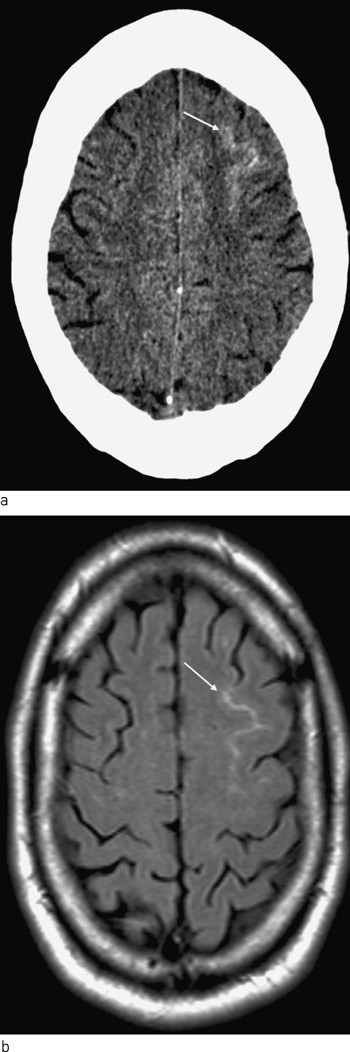

På mistanke om subaraknoidalblødning ble det rekvirert CT caput. På denne var det tegn til subaraknoidalt blod beliggende over konveksitetene langs gyri på begge sidene av falx cerebri. Differensialdiagnostisk kunne det dreie seg om eksudasjon av proteinrik væske. Det ble deretter utført MR cerebrum med arteriell og venøs angiografi, som viste multippel sklerose-forandringer, som ved tidligere undersøkelser, samt subaraknoidalt blod som beskrevet. Aneurismer eller karmisdannelser ble ikke påvist. I figur 1 er CT- og MR-funnene vist. Spinalvæskeanalyse 12 timer senere viste rikelig med erytrocytter, men fravær av bilirubin. Proteinverdien og leukocyttallet i spinalvæsken var lett forhøyet, henholdsvis 875 mg/l og 6 · 10⁶/l, noe som også kunne forklares av multippel sklerose.

Sykehistorien, kliniske funn, CT- og MR-bilder var altså forenlig med subaraknoidalblødning, men noe åpenbart blødningsfokus kunne ikke påvises. Den symmetriske lokaliseringen av blodet over konveksitetene på begge sider av falx cerebri var også uvanlig.